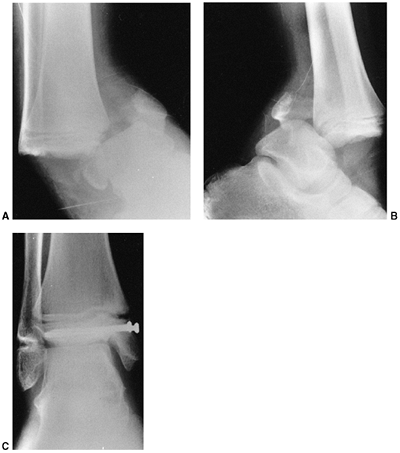

fractures, in which the capitellum is posterior to the anterior humeral

line, have an unacceptable amount of extension. Many of these are

stable after closed reduction and casting in 90 to 100 degrees of

flexion (130). When more than 100 degrees of

flexion is required for maintenance of reduction, percutaneous pinning

is recommended, with immobilization in less than 90 degrees of flexion (131). Weekly follow-up for 2 weeks is recommended following closed management to diagnose and treat any loss of reduction.

![]() |

|

Figure 33.17 Type II supracondylar humerus fracture with medial impaction and varus alignment. A, B:

Anteroposterior and lateral views of a type II supracondylar humerus fracture with medial impaction. Note that although there is little displacement on the lateral view, the Baumann angle is 0 degrees on the anteroposterior. C, D: Anteroposterior and lateral intraoperative views of the distal humerus after the impacted fracture was reduced and fixed with divergent lateral pins. Note that on the anteroposterior, the Baumann angle is restored, and on the lateral, the anterior humeral line intersects the capitellum. The reduction was maintained during the postoperative period. |